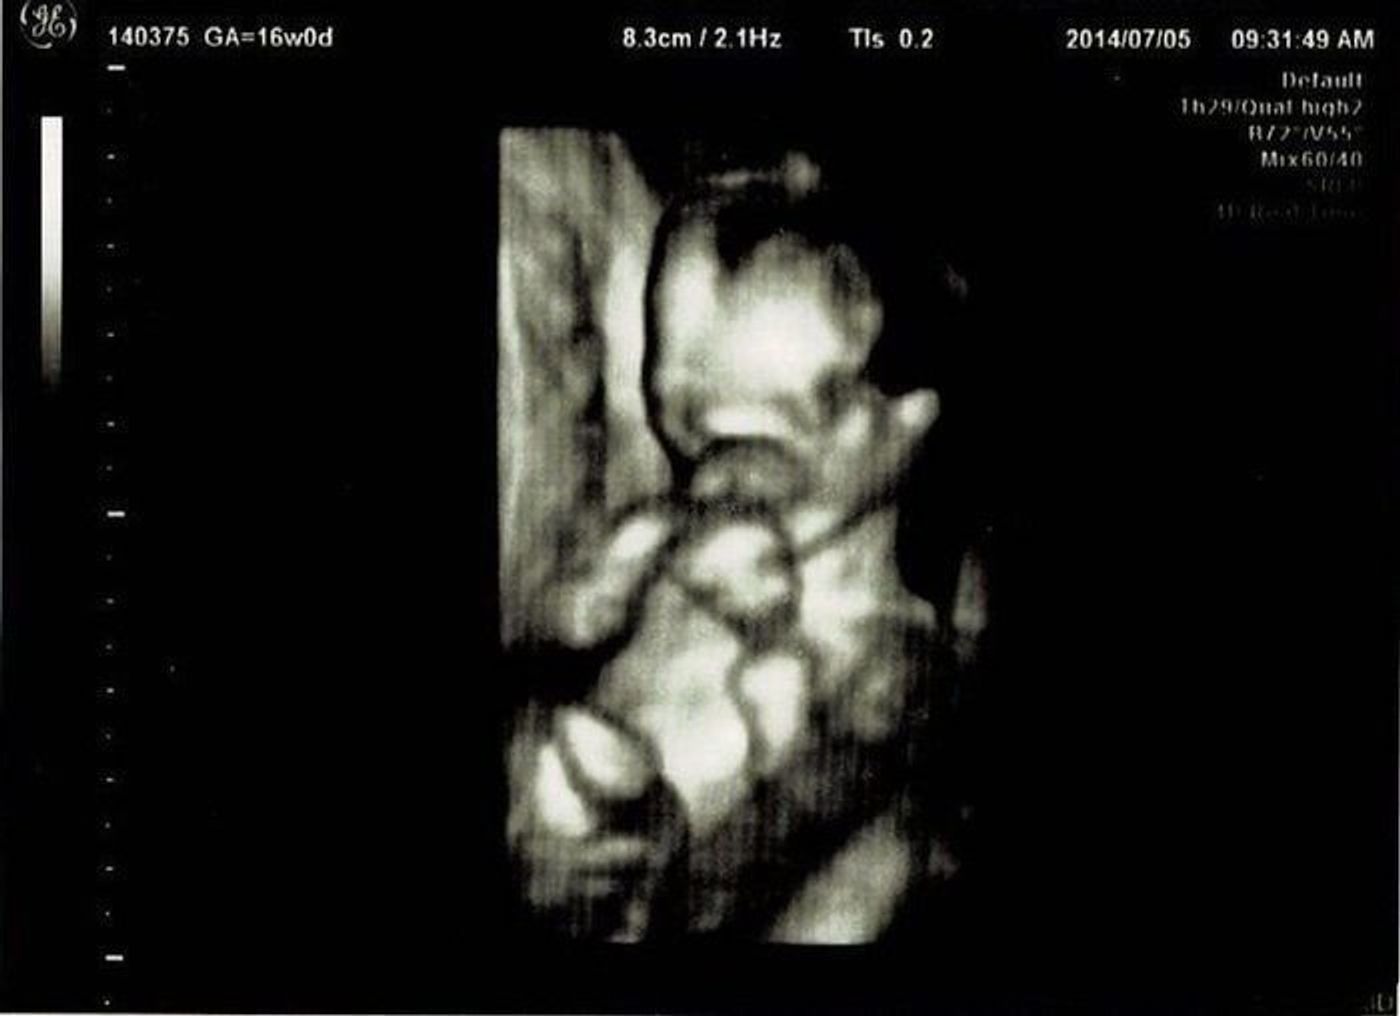

女の子はなかなか性別確定に至らない 妊娠16週、つまり妊娠5ヶ月には、比較的胎児と母体の状態が安定した、安定期と呼ばれる時期に入ります。 引用赤ちゃんが女の子の場合で 妊娠5ヶ月(16週・17週・18週・19週)の経過とエコー写真 16週0日(16w0d) 5ヶ月の妊婦健診でした。 「性別わかるかな・・・?」とワクワクしていたのですが、残念ながらこの 胎児の性別がエコーで判別できるのは、一般的に早くて妊娠5か月頃。 はっきりとわかるのは7か月頃の人が多い。 私の場合、19週3日のエコーで医師から男の子と告げられました。 希

男の子の性別判定はいつから可能? 男の子の性別判定はいつから可能なのでしょうか? 男の子の性別判定は比較的早く、早くて15週・16週ごろからシンボルが見えてくる ようです! 女の子の性別判定はいつから可能? 女の子の性別判定はいつから可能なのでしょうか? 男の子も女の子も外性器がしっかりと形成され、 性別判定ができるようになってくるのは大体ど妊娠16週5日(16w5d)の赤ちゃんのエコー写真です。投稿も募集しています。 性別がわかるかなぁーとドキドキして行った検診!残念ながら赤ちゃんは見せてくれませでした。笑 こっちを向いて笑ってる写真 ばばちゃんには宇宙人と言われたけどママに

妊娠14週にエコー検査を受けると、より人間に近い体つきの胎児が確認できるでしょう。 胎児の性別は受精した瞬間に決まっていますが、超音波検査で性別を調べられる時期の目安は妊娠14 妊娠16週未満まで検査を受けていただけるため、出生前診断を ちなみに 胎動は 16 週から 感じてましたが、どっちが先に動いてくれたのかこれも分かりません。 18週の双子エコー写真性別と位置、大きさがはっきりしてくる時期 18週妊娠週 16w4d 1ヶ月ぶり2回目の健診でした! はじめての腹部エコー、そして4Dでドキドキでした(笑)寝て居たようでしたが、心臓は元気に動いていて安心。 この時のエコーでしっかりおチン